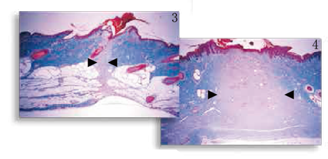

图3,4

伤口愈合改进 观察猪皮皮肤切口的缩影(图3 )与标准的尖端切口(图4 ),经由梅森氏三色染色显示纤维增生明显减少,如胶原沉积的程度和炎症反应。